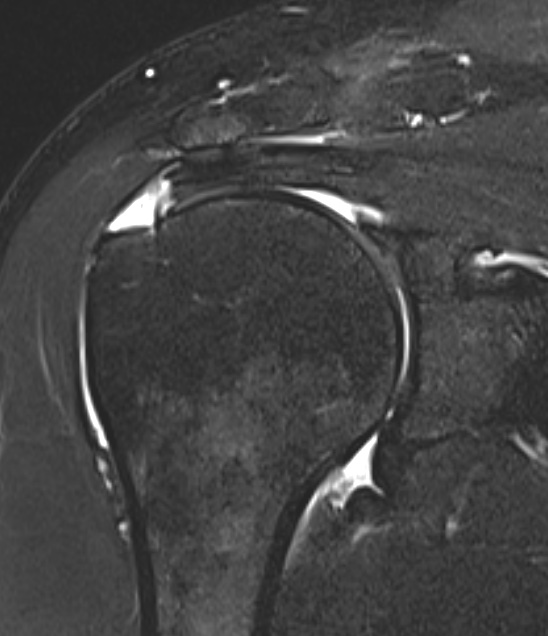

Full thickness rotator cuff tears

Partial bursal sided tear Partial articular sided tears

Measure tear in the coronal and sagittal plane

Large full thickness tear of supraspinatus and infraspinatus tendon - retracted to midhumeral head